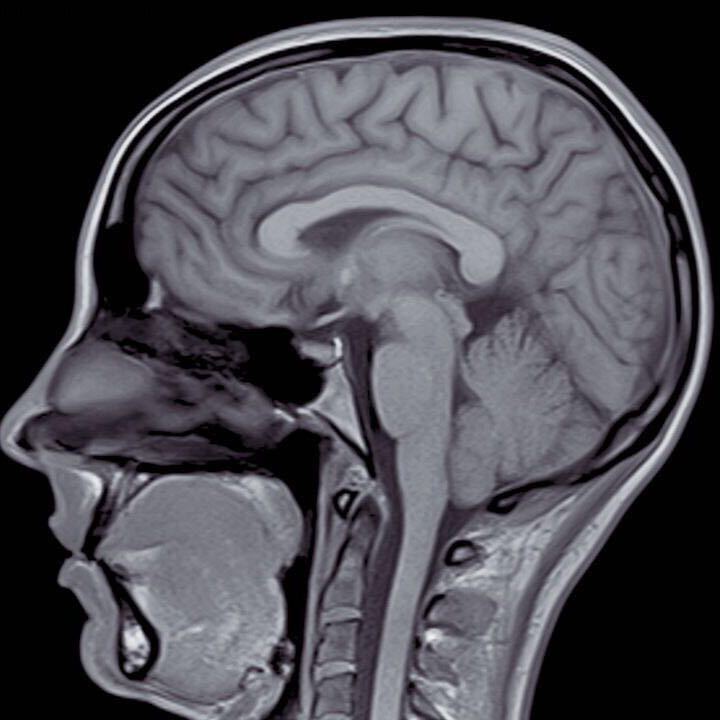

90Y树脂微球是治疗肝癌和肝转移瘤的放射性核素内照射技术,通过介入技术把90Y树脂微球这种放射性核素物体直接送达肝脏肿瘤内部,